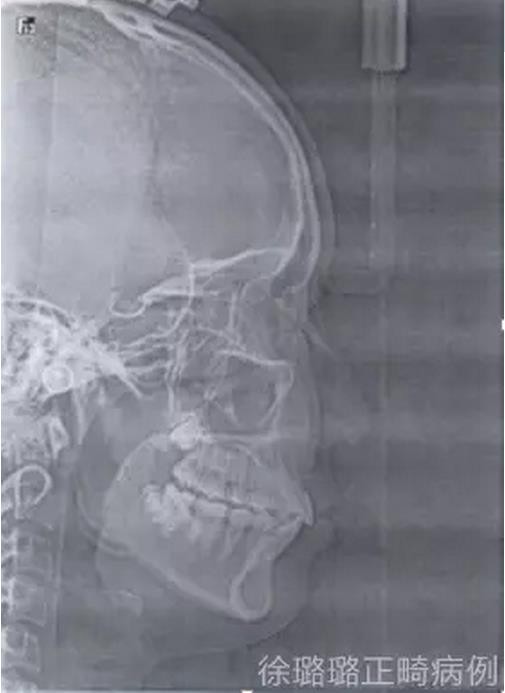

面部分析:面部左右對稱、和諧;凹面型得到改善。

咬合分析:建立了雙側(cè)磨牙及尖牙 I 類關(guān)系;前牙覆牙合、覆蓋關(guān)系正常;上下中線基本與面中線一致。

該病例通過口腔外科導(dǎo)萌術(shù)與正畸的聯(lián)合治療,非拔牙矯治上頜雙側(cè)尖牙埋伏阻生?;颊叱C治結(jié)束后,面部左右對稱,凹面型得到改善,上下唇突度未因非拔牙矯治造成進一步前突,顴骨突出得到掩飾,下頜偏斜得到糾正,上下中線基本與面中線一致;上頜前牙突、下牙列擁擠得以解除;雙側(cè)上頜尖牙成功導(dǎo)萌,磨牙、尖牙建立了中性關(guān)系,前牙覆牙合、覆蓋關(guān)系正常。